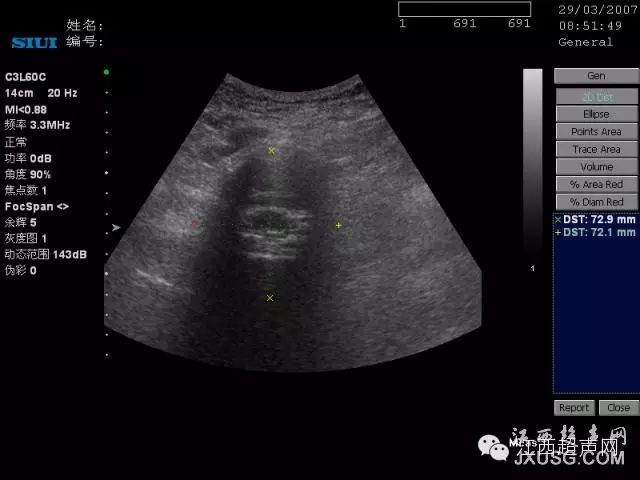

9.比较瘦小的人,在腹部探查时,容易把臀部肌肉当成盆腔内的肿块: